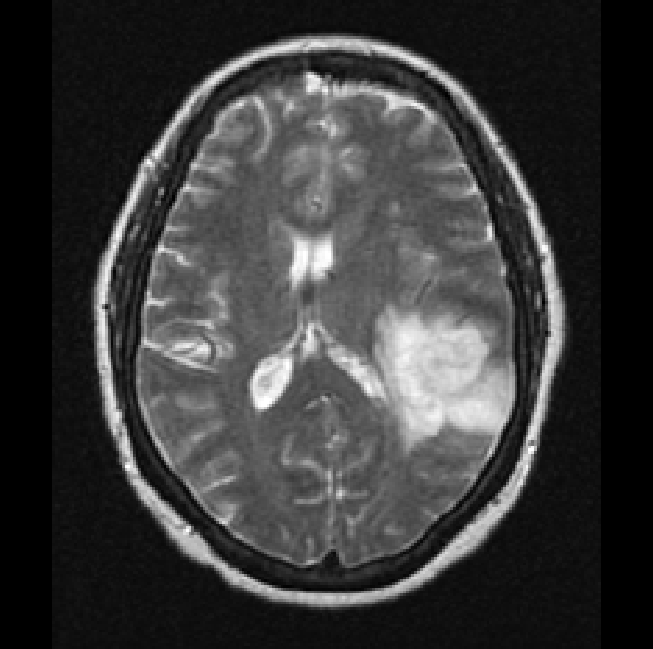

Finally, we considered two examples of scans that were incorrectly predicted by our method, see Figure 9. These two examples were chosen because our network assigned high prediction scores to the wrong classes for these cases. Figure 9(a) shows an example of a grade II, IDH mutated, 1p/19q co-deleted glioma that was predicted as grade IV, IDH wildtype by our method. Our method’s prediction was most likely caused by the hyperintensities in the post-contrast T1w scan being interpreted as contrast enhancement. Since these hyperintensities are also present in the pre-contrast T1w scan they are most likely calcifications, and the radiological appearance of this tumor is indicative of an oligodendroglioma. Figure 9(b) shows an example of a grade IV, IDH wildtype glioma that was predicted as a grade III, IDH mutated glioma by our method.